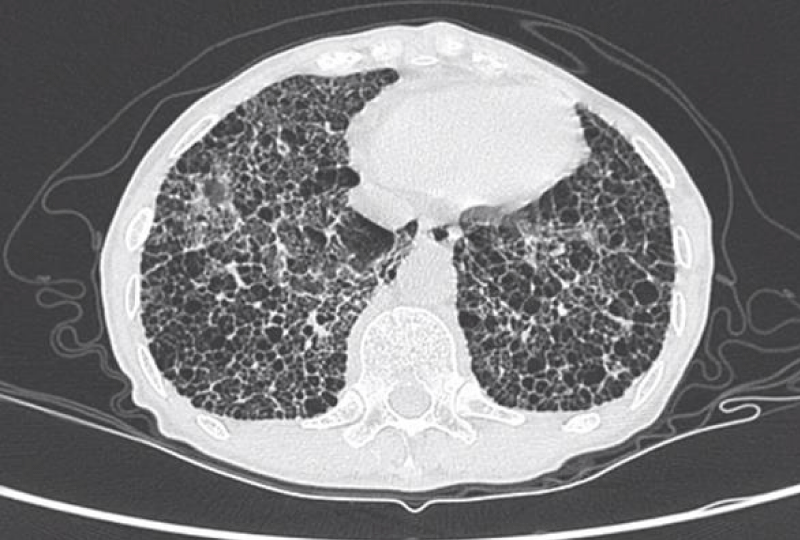

HRCT images

The most common presentation on HRCT were ground-glass opacities, showed 79.3% (92 patients). Secondly, 74.1% patients showed interlobular septal thickening, followed by reticular opacities(58.6%), intralobular interstitial thickening(45.7%), mediastinal lymph node enlargement(36.2%), nodules(30.2%), honeycomb cysts (29.3%), traction bronchiectasis(21.6%), stripes(17.2%), pleural thickening(14.7%), pleural effusion(10.3%), dilation of the esophagus(6.9%), emphysema(6.9%), bullae(5.2%), consolidation(5.2%), subpleural line(0.9%) (Figures 1-9).

Figure 1: Ground-glass opacities.

HRCT represents a reliable, noninvasive and repeatable tool for detecting and monitoring ILD in patients with SSc. The main HRCT findings in SSc-ILD are signs of GGO, interlobular septal thickening, intralobular septal thickening, reticular opacities; honeycombing, traction bronchiectasis and nodules can also be observed.

GGO as the most common presentation on HRCT, were hazy increased attenuation of lung, presented nodular, piece-like round or irregular shape on HRCT, with preservation of bronchial and vascular margins, mainly distributed in the lung periphery or diffusely distributed symmetrical, always suggested the early-stage or active-stage [6,7].